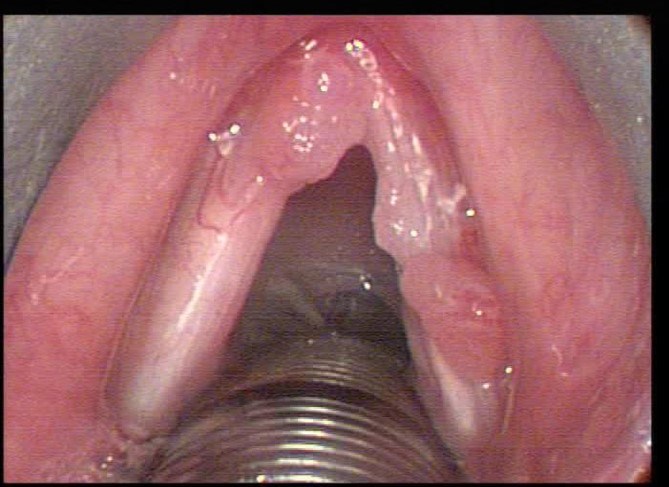

Непрямая микроларингоскопия: вход в гортань свободный, надгортанник не изменен, на голосовых складках с обеих сторон папилломатозные массы, занимающие до 2/3 голосовых сладок (рис 1). Смыкание неполное, голосовая щель широкая, дыхание свободное.

Рис. 1. Эндоларингеальная картина до операции